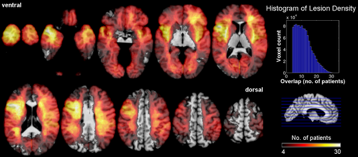

Large-Scale Lesion-Symptom Mapping

Finally, in addition to focusing on the specific neuroanatomical regions implicated in emotion and social cognition (amygdala, and ventromedial prefrontal cortex), we have taken a more whole-brain approach and studied larger samples of patients with lesions distributed all over the brain.  Our earlier work did this in a rather crude way, generating overlap images of lesions.  Later, we used nonparametric voxel-based lesion-symptom mapping, which generates voxelwise statistics.

These studies have revealed more distributed neural systems that contribute to cognitive processes like emotion recognition, decision-making, and intelligence.  This work is ongoing, with collaborators Daniel Tranel at the University of Iowa, and Jan Glaescher at the University of Hamburg.

lesion overlaps

Above: Lesion overlaps in patients from the Iowa patient registry.  In these images the color encodes the density of lesion overlaps in 250 patients.  Note that most of the brain is sampled, but not homogeneously, resulting in a complex anatomical distribution of statistical power to detect potential deficits.